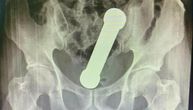

ŽALIO SE NA BOLOVE Lekari zanemeli kad su videli rendgenski snimak: Iz rektuma mu izvađen teg od 2 kilograma!